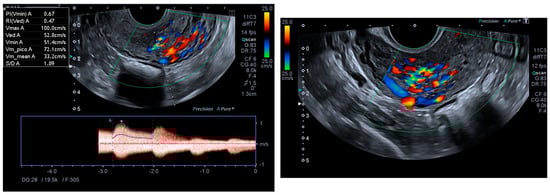

Ultrasonography showed an endometrial cavity occupied by a protruding formation in the uterine cavity measuring 38 × 15 mm, compatible with a uterine AVM (Figure 1). The presence of vascularisation of the right lateral uterine wall was noted, and pulsed Doppler showed a peak systolic velocity > 100 cm/s (Figure 2).

Figure 1. Transvaginal ultrasound with suspected uterine arteriovenous malformation.